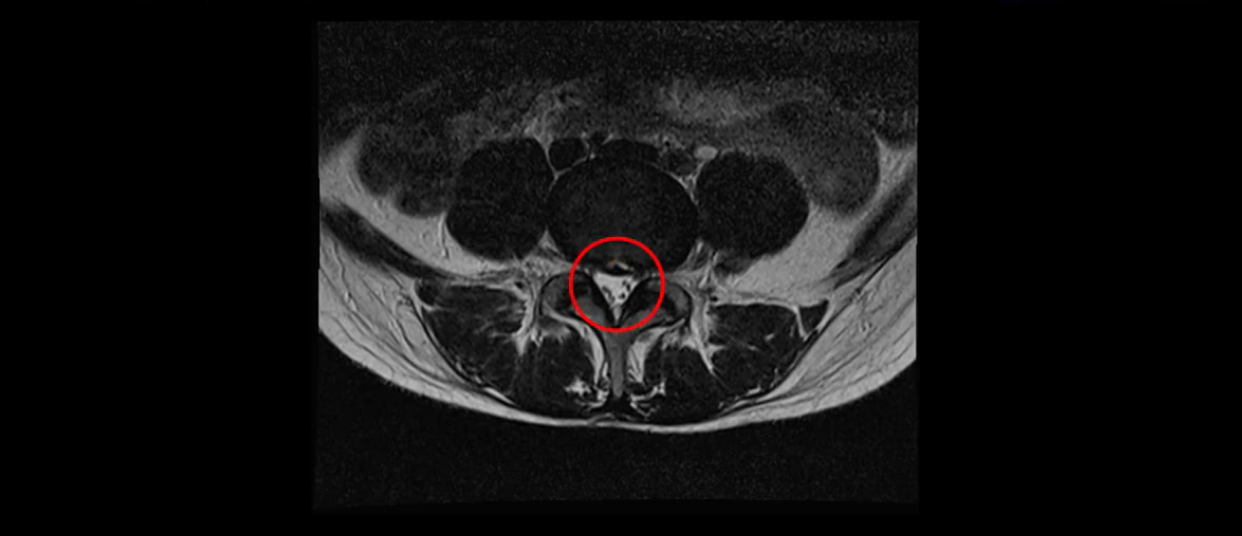

우선 이분의 MRI를 보고 먼저 설명을 드린 후 이런 환자분들의 통증의 원인은 무엇인지, 그리고 치료는 어떻게 해야 하는지 자세히 설명 드리겠습니다.

이분 MRI를 보시면 두 마디의 퇴행성디스크가 있습니다. 그리고 디스크가 조금씩 밀려 나와 있고요. 그런데 디스크 탈출 정도는 두 마디 다 심하지 않습니다. 4번 5번에는 디스크 탈출이 약간 있고,

척추관협착도 약간 진행이 되고 있고요.

5번 1번은 디스크 탈출이 가운데 쪽으로 살짝 있습니다.

또한 양쪽 신경 가지가 빠져나가는 추간공은 매우 넓은 상태입니다.

중요한 것은 이 정도 경미한 탈출과 협착으로는 양쪽 다리가 저리고 아플 수가 없습니다.

이분 MRI를 보시면 퇴행성디스크가 있고 약간의 협착이 있지만 이 정도의 퇴행성디스크와 협착으로는 신경이 눌려서 양쪽 다리가 저리고 아픈 증상이 나올 수가 없습니다. 그래서 MRI와 이 환자분의 다리 증상이 매치가 안 된다고 하는 의사들이 많은 겁니다.